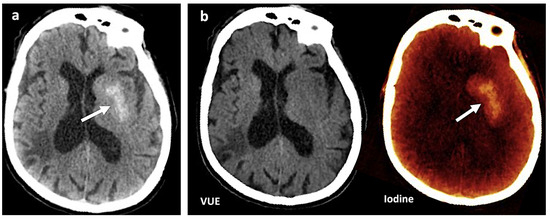

Figure 1.

Contrast media extravasation can mimic hemorrhage after endovascular thrombectomy. (a) A 120 kVp-like brain image (similar to conventional single-energy imaging) shows a hyperdense area (white arrow) in the left basal ganglia following thrombectomy in a patient with ischemic stroke. Hemorrhagic transformation must be ruled out (b). Virtual non-contrast (VUE) and color-coded iodine overlay map evidence that this hyperdense area is not depicted on VUE while it remains on the iodine map (white arrow), representing contrast staining.